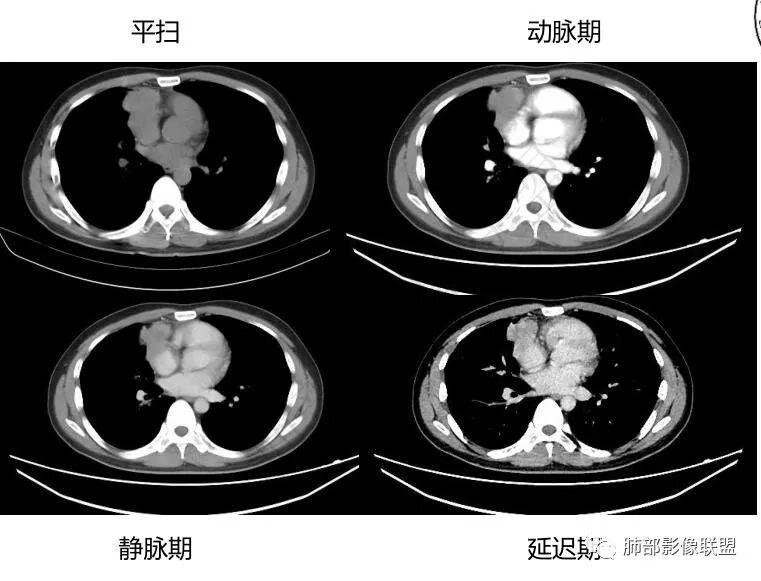

中青年男性,前纵膈偏右侧软组织肿块,形态不规则,有分叶,密度均匀,增强病灶轻中度强化,内部可见低或无强化区域,病灶与血管周围间隙分界不清晰,考虑恶性或交界性肿瘤,胸腺类癌>生殖细胞瘤>淋巴瘤。

青年男性,前上纵隔占位,渐进强化,坏死不明显,nse稍高,首先考虑类癌,鉴别精原,内胚窦瘤,需要结合实验室检查HCG,AFP等

中年男性,胸痛,既往健康,前上纵隔软组织肿块,形态不规则,密度不均,没有血管包埋及受侵征象,呈不均匀强化,考虑胸腺瘤,鉴别淋巴瘤,精原细胞瘤,胸腺癌

前纵隔右侧见大肿块,边缘清,同侧内乳动脉增粗,渐进性延迟强化明显,强化密度不均匀,中心见偏低密度灶,上腔静脉内后侧推压移位(提示肿块质地偏硬),副神经节瘤,与巨淋巴细胞增生症鉴别。

青年男性,咳嗽,右上前纵隔不规则肿块,分叶,上腔静脉受压,内乳动脉增粗,延迟强化明显,坏死不明显,考虑来源纵隔,胸腺瘤,淋巴瘤,神经源性肿瘤都可以,比较年轻,猜个淋巴瘤吧。神经源性肿瘤代排。

青年男性,前纵隔软组织肿块,偏右侧生长,边缘多发分叶,包绕临近血管生长,增强后轻度强化,并呈渐进性,可见点状坏死,考虑胸腺瘤,鉴别淋巴瘤,生殖细胞肿瘤,巨淋巴结增生症

青年男性,前纵隔偏右侧软组织肿块,密度均匀,分叶,渐进性不均匀强化,可见点状坏死,考虑胸腺瘤,鉴别生殖细胞肿瘤,淋巴瘤,CD。

青年男性,前纵隔偏右侧肿块,分叶,与邻近血管分界不清,上腔静脉受压,不均匀渐进强化,点状坏死,考虑胸腺瘤,鉴别胸腺类癌

男性32岁前纵隔偏右侧见一不规则软组织影,边缘毛刺,呈分叶征,同侧内乳动脉增粗,延迟性强化,内见条状分隔影,考虑胸腺瘤(B1、2,临界年龄段,分隔有些提示倾向),NSE轻度升高,中度强化,类癌代排。内胚窦及精原等生殖细胞肿瘤影像不符合,建议结合实验室检查

年轻男性,NSE稍高,前纵隔偏右侧不规则实性肿块,平扫密度均匀,增强渐进性不均匀强化,内见低密度区,似见条样分隔。考虑为胸腺瘤,建议实验室检查HCG,AFP等鉴别生殖细胞肿瘤

青年男性,前上纵隔占位,偏侧生长,边缘不规则,可见分叶及分隔,内见少量无强化低密度区,常规考虑胸腺瘤,NSE稍偏高一点,会不会是实验室误差?

前纵隔右侧不规则软组织肿块,边缘欠清,增强渐进性强化,内见星状无强化分隔,部分分隔延迟强化,青年男性,首先考虑精原细胞瘤,鉴别胸腺瘤,NSE轻度升高,类癌也需鉴别!

前纵隔肿块,轻度分叶,边界不清楚,延迟强化,可见分隔,倾向恶性或具有一定侵袭性病灶。